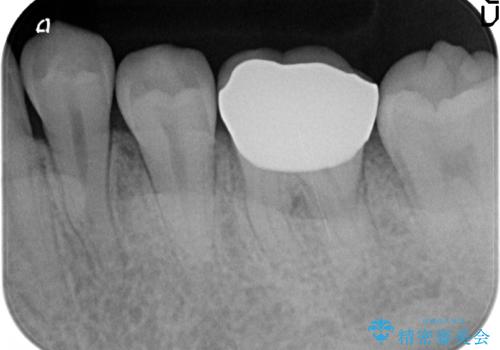

- 左下6の歯が欠けてしまったので診て欲しいといらっしゃった方の症例です。

虫歯除去後、オールセラミッククラウンによる補綴を行いました。

今回用いたオールセラミッククラウンはジルコニアフレームという白い素材の上にセラミックを盛っているため、審美性が非常に高いのが特徴です。

また、ジルコニアは人工ダイヤモンドの材料にも使われているほど高い強度を持っており、そのためオールセラミッククラウンは審美性だけでなく、奥歯やブリッジの補綴も可能とするクラウンです。